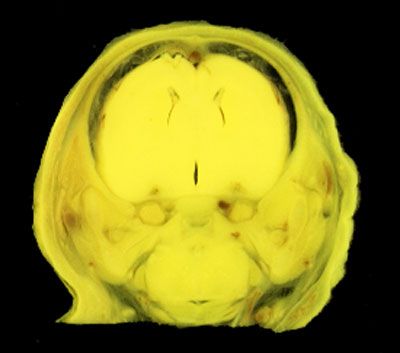

NORMAL APPEARANCE OF THE BOUIN'S FLUID FIXED RAT HEAD

The images below show the normal appearance of Bouin's fluid fixed head sections in specimens at Day 21 of gestation (day mating observed = Day 0).

It is essential that both sides of each section is examined so that structures that exist is several sections can be visualised by the examiner in 3D.

Learning objective: Compare the diagrams with your own specimens and identify all of the structures that have been labelled.

Unlabelled Images